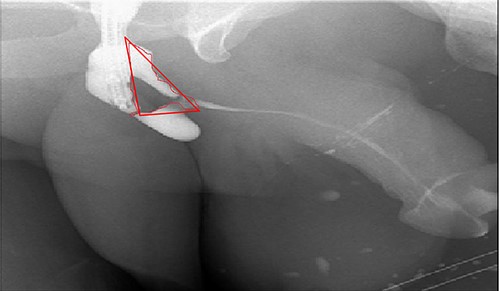

In the beginning, an inverted Y midline perineal skin incision was made extending from the base of the scrotum to just above the anus. There was an extensive adhesion reaching up to the Colle’s fascia and they were incised. Then, a cystoscope was introduced through the suprapubic channels and a guidewire was inserted through the pinpoint stricture. An 18-French Red Rubber Catheter was advanced per urethral meatus to the stricture. The urethra was dissected from the corpora cavernosa and rotated. After that, the urethra was incised dorsally over the distal tip of the catheter to open lumen A over the previously inserted guidewire (Fig. 1, lumen A). Once lumen A was completely open, the other channel was ventral to the scarred urethral plate. Therefore, the decision was to completely excise this channel to leave the ventral service lined by the previously placed fasciocautonous flap. The resected area is marked by red line in Fig. 4. Then, refashioning the proximal part and distal flap to form the ventral covering of the urethra. After that, harvesting the BMG was done. The harvested BMG was tailored and placed dorsally where it was split-fixed to the corporal body. The proximal and distal apical edges of the graft were sutured to the corresponding dorsal wall of the corpus spongiosum using an interrupted full-thickness 5–0 PDS. After that, the lateral edge of the corpus spongiosum was secured to the lateral aspect of the graft and the underlying tunica albuginea of the corpora using a 5–0 PDS suture on each side allowing the flap to rotate to its original position. Before completion, a 16-French urethral catheter was advanced easily into the bladder. Subcutaneous tissues that included a part of the bulbous spongiosum muscle and Colle’s fascia were closed in a continuous fashion using 3–0 Vicrl. Finally, the skin was closed using 4–0 Vicry-Rapide. The postoperative course was uneventful. Four days later, he was discharged home in a healthy condition. The patient recovered from surgery.

Antegrade urethrogram with the resected area marked in red line.